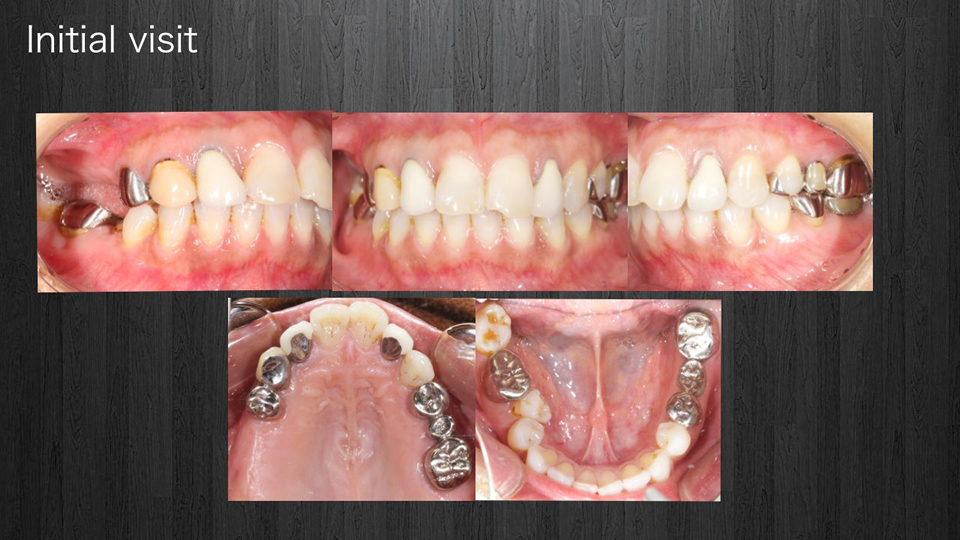

< 症例2 >

- 治療期間:28ヶ月

- 治療回数:145回

- 治療歯数:28歯

- 費用:全顎矯正治療80万円 インプラント治療:195万円 上部セラミック:300万円

- リスク:メンテナンスを怠ると、インプラント周囲炎になる可能性があります。

- インプラント手術には合併症が伴う場合があります。

- 治療期間は治癒の状態により前後する場合があります。